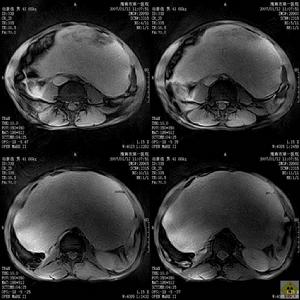

(二)胸部CT和HRCT

是診斷淋巴管平滑肌瘤的重要手段。胸部CT尤其是HRCT可以明確顯示出普通胸片顯示不清的肺囊腫。淋巴管平滑肌瘤的肺囊腫具有顯著特點,為全肺均勻分布的大小不等的薄壁囊腫,直徑在0.5~5cm之間,囊壁的厚度一般<2mm。早期囊腫較小,隨病情發展囊腫加大。這類形態的囊腫發生率為100%,是診斷淋巴管平滑肌瘤的重要依據。早期約50%患者出現磨玻璃影。在CT上能看到結節陰影者僅5%左右,為腫大的囊腫壓迫周圍過度生長的平滑肌細胞所致。如出現片狀陰影則提示出血。Sherrier等報告的8例LAM患者中4例發現縱隔淋巴結腫大。以HRCT定量測定囊腫面積與測定肺容量、彌散功能、運動試驗所評價的疾病嚴重程度相符合,故HRCT即可用於診斷又可判定預後。CT或HRCT可發現腹後壁、腹腔、腎臟、盆腔的病變。